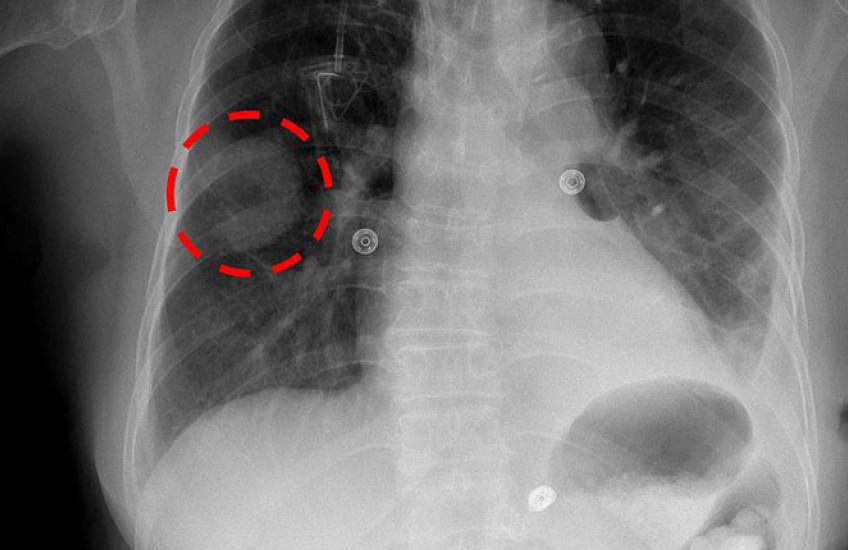

The researchers examined how AI tools affected the performance of 140 radiologists on 15 X-ray diagnostic tasks — how reliably the radiologists were able to spot telltale features on an image and make an accurate diagnosis. The analysis involved 324 patient cases with 15 pathologies — abnormal conditions captured on X-rays of the chest.